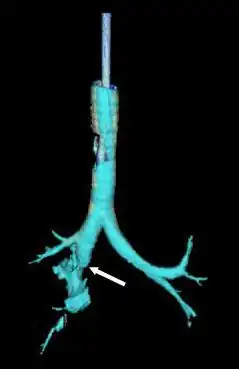

![]() Reconstrucción de la tráquea y los bronquios con tomografía computarizada de rayos X que muestra la interrupción del bronquio principal derecho con una elucidación anormal (flecha) | ||

La radiografía de tórax es la técnica de imagen inicial usada para diagnosticar la LCT.[17] La radiografía puede no tener ningún signo en un paciente por lo demás asintomático.[15] Las indicaciones de LCT vistas en las radiografías incluyen deformidad en la tráquea o un defecto en la pared traqueal.[17] La radiografía también puede mostrar enfisema cervical, aire en los tejidos del cuello.[2] Las radiografías también pueden mostrar lesiones y signos acompañantes como fracturas y enfisema subcutáneo.[2] Si se produce un enfisema subcutáneo y el hueso hioides aparece en una radiografía a una altura inusual en la garganta, puede ser un indicio de que la tráquea ha sido seccionada.[4] También se sospecha de LCT si un tubo endotraqueal aparece en una radiografía fuera de lugar, o si su manguito parece estar más lleno de lo normal o sobresale a través de un desgarro en las vías respiratorias.[17] Si se desgarra un bronquio en toda su extensión, el pulmón puede colapsarse hacia fuera, hacia la pared torácica (en lugar de hacia dentro, como suele ocurrir en el neumotórax), porque pierde la unión al bronquio que normalmente lo mantiene hacia el centro.[6] En una persona tumbada boca arriba, el pulmón se colapsa hacia el diafragma y la espalda.[23] Este signo, descrito en 1969, se denomina signo del pulmón caído y es patognomónico de LCT (es decir, es diagnóstico de LCT porque no se produce en otras afecciones); sin embargo, sólo se produce en raras ocasiones.[6] Hasta en uno de cada cinco casos, las personas con traumatismo contuso y LCT no presentan signos de la lesión en la radiografía de tórax.[23] La TC detecta más del 90% de los TLC resultantes de traumatismo contuso,[3] pero ni la radiografía ni la TC sustituyen a la broncoscopia.[6]